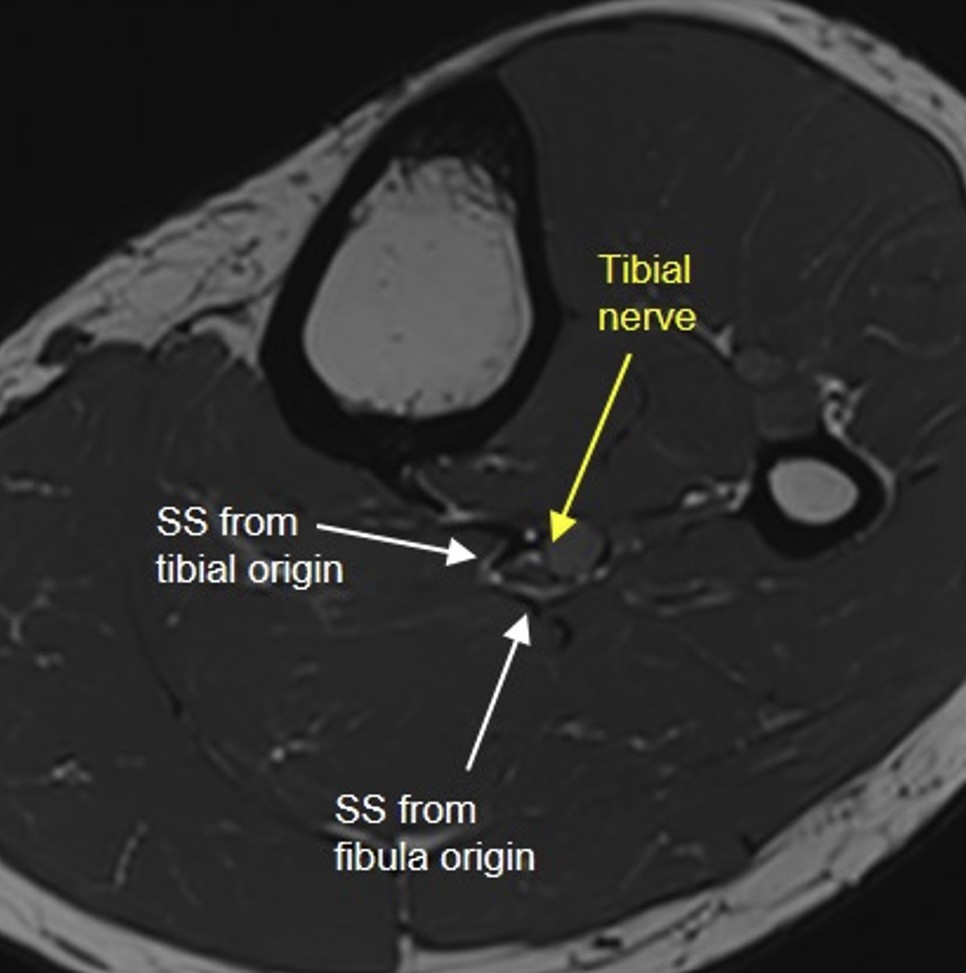

complex baker cyst ( rid3892 )